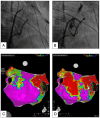

Atrial fibrillation is the most common sustained cardiac arrhythmia with a significant impact on quality of life in terms of symptoms and reduction of functional status. Also, it is associated with an increased risk of mortality, stroke, and peripheral embolism. Catheter ablation for atrial fibrillation has become a well-established treatment, improving arrhythmia outcomes without increasing the risk of serious adverse events compared to antiarrhythmic drug therapy. The field has undergone significant advancements in recent years, yet pulmonary vein isolation continues to be the cornerstone of any atrial fibrillation ablation procedure. The purpose of this review is to provide an overview of the current techniques, emerging technologies, and future directions.

Keywords: atrial fibrillation; catheter ablation; posterior wall isolation; pulmonary vein isolation; pulsed field; vein of Marshall.